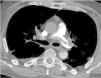

A 56-year-old man presented with profound shock and unresponsive hypoxemia. Pulmonary embolism was suspected given the extremely dilated right ventricle with septal flattening. It was decided then to start peripheral veno-arterial extracorporeal membrane oxygenation (VA-ECMO) through bedside cannulation. 72h later, the patient was on unfractionated heparin, had recovered from multiorgan failure without neurological impairment and vasopressors had been withdrawn. However, persistent hypoxemia and right ventricle dysfunction challenged ECMO weaning. A computed tomography confirmed the diagnosis (Fig. 1) and provided evidence of the harlequin syndrome (Fig. 2) as the two bloodstreams, the native cardiac output and oxygenated ECMO return, meet in the watershed area. Subsequently, the patient underwent a successful transcatheter pulmonary thromboaspiration (Fig. 3) and could be weaned from mechanical ventilation and ECMO the following days. He was discharged two weeks later without further complications.